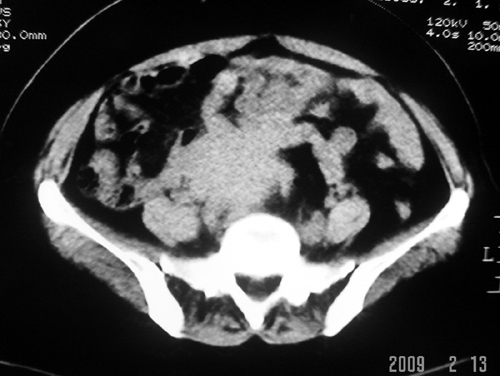

以下是引用余辉在2009-2-14 8:37:00的发言:[br]宫颈左后壁见较大低密度肿物影且向左后上方突出,宫腔内见大片状低密度区,考虑宫颈肿瘤,宫颈癌可能性大,伴宫腔积液或转移